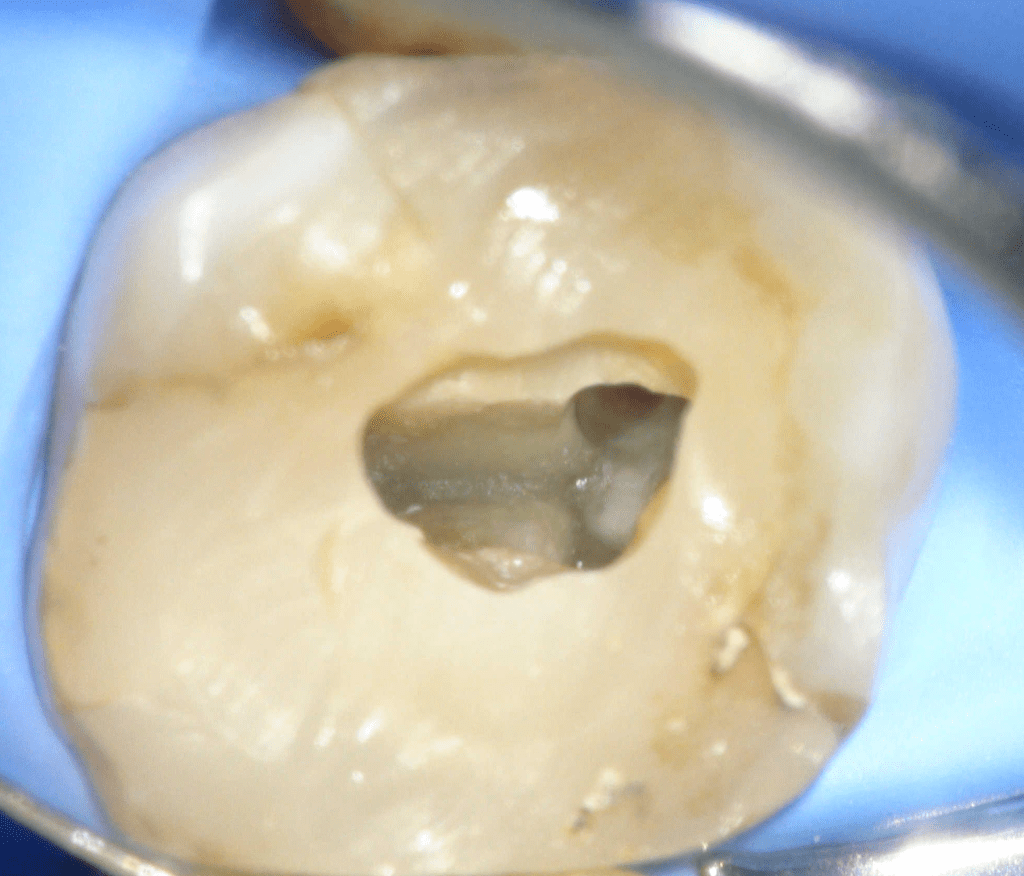

Fisura, remoción amalgama para explorar